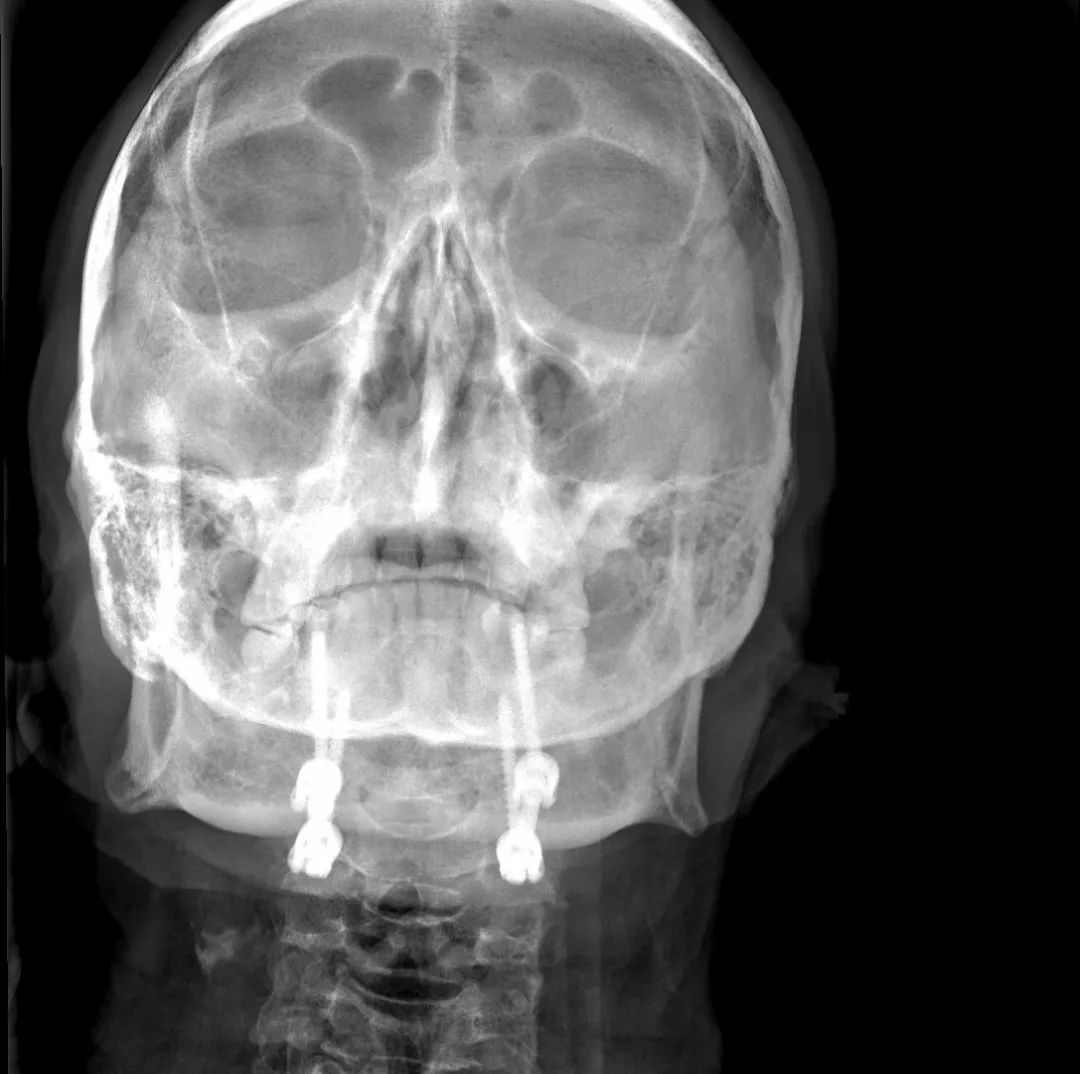

患者,男性,75岁,因外伤致颈部疼痛伴活动受限7天入院。患者入院前在当地医院确诊为:枢椎齿状突骨折Anderson-D’Alonzo分型Ⅱ型。

对于本患者来说,齿状突骨折后导致寰枢椎不稳,极易引起延髓或椎动脉损伤,严重者当场死亡。但患者同时合并严重胸腰椎后凸畸形,颈部后伸受限,不具备前路手术条件,这就给其治疗更增加了额外的困难。而由于手术部位延髓及椎动脉等血管神经密布,手术难度高、风险极大,稍有不慎,患者就会有生命危险。而患者家属在了解到手术的危险性后,曾自行到上级医院咨询专家,上级医院专家考虑围手术期死亡的风险,对于本例患者亦不愿提供手术治疗的机会。

患者经充分咨询了解,选择了枣庄市立医院脊柱外科主任王存平为其治疗。面对患者和家属期盼的目光,王存平明白这是患者最后的希望,故而没有胆怯和退缩,大胆提出了齿状突骨折后路切开复位C1、2椎弓根钉棒系统固定的手术方案。由于患者年龄较大,存在脊柱严重后凸畸形,俯卧位极度困难,全麻插管难度大,麻醉风险极大。麻醉科李传东和宓云飞医师克服重重困难,成功完成麻醉。在他们得力的麻醉和监护下,王存平仔细分离、细心操作,每一步都确保动作稳稳完成,最终成功实施了手术。

经过全程监护和系统治疗,患者术后恢复良好,骨折解剖复位,复查X线及CT显示固定位置佳,术后3天下地行走,术后4天即出院回家休养。